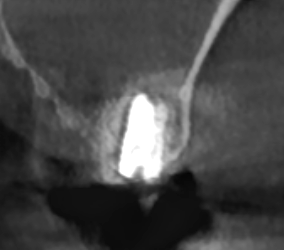

앞뒤 좌우 3차원적인 자세한 분석을 위해

ct 촬영을 시행

디지털 기기의 분석 결과

3mm 정도의 아주 얇은 뼈가 확인되었습니다.

어금니 임플란트를 심기 위해서는

최소 8~10mm의 길이가 필요합니다.

어느 정도로 부족한지 감이 잡히시나요~?

게다가 상악동 공간에 염증까지...